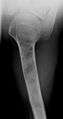

On radiographs, streaks of low density are seen projecting through the diaphyses into the epiphyses of the long bones, due to ectopic cartilage deposits. With age, the cartilage may calcify in the typical "snowflake" pattern.